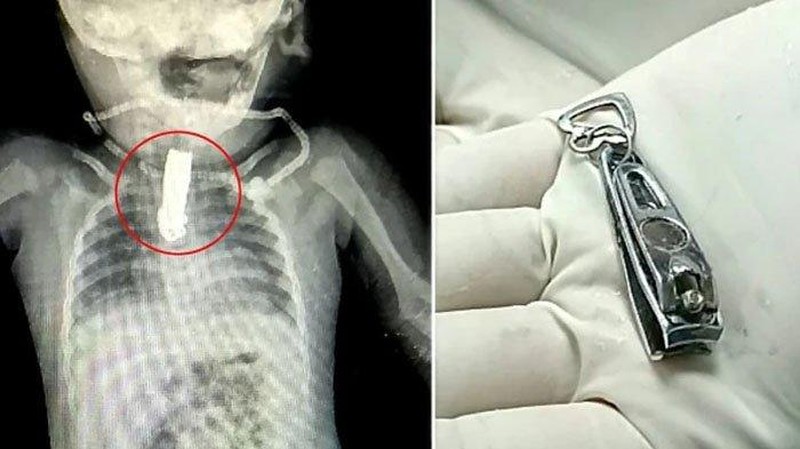

Menurut keterangan, tim medis mengeluarkan benda itu dalam operasi panjang selama satu jam. (Foto: Newslion/SWNS)